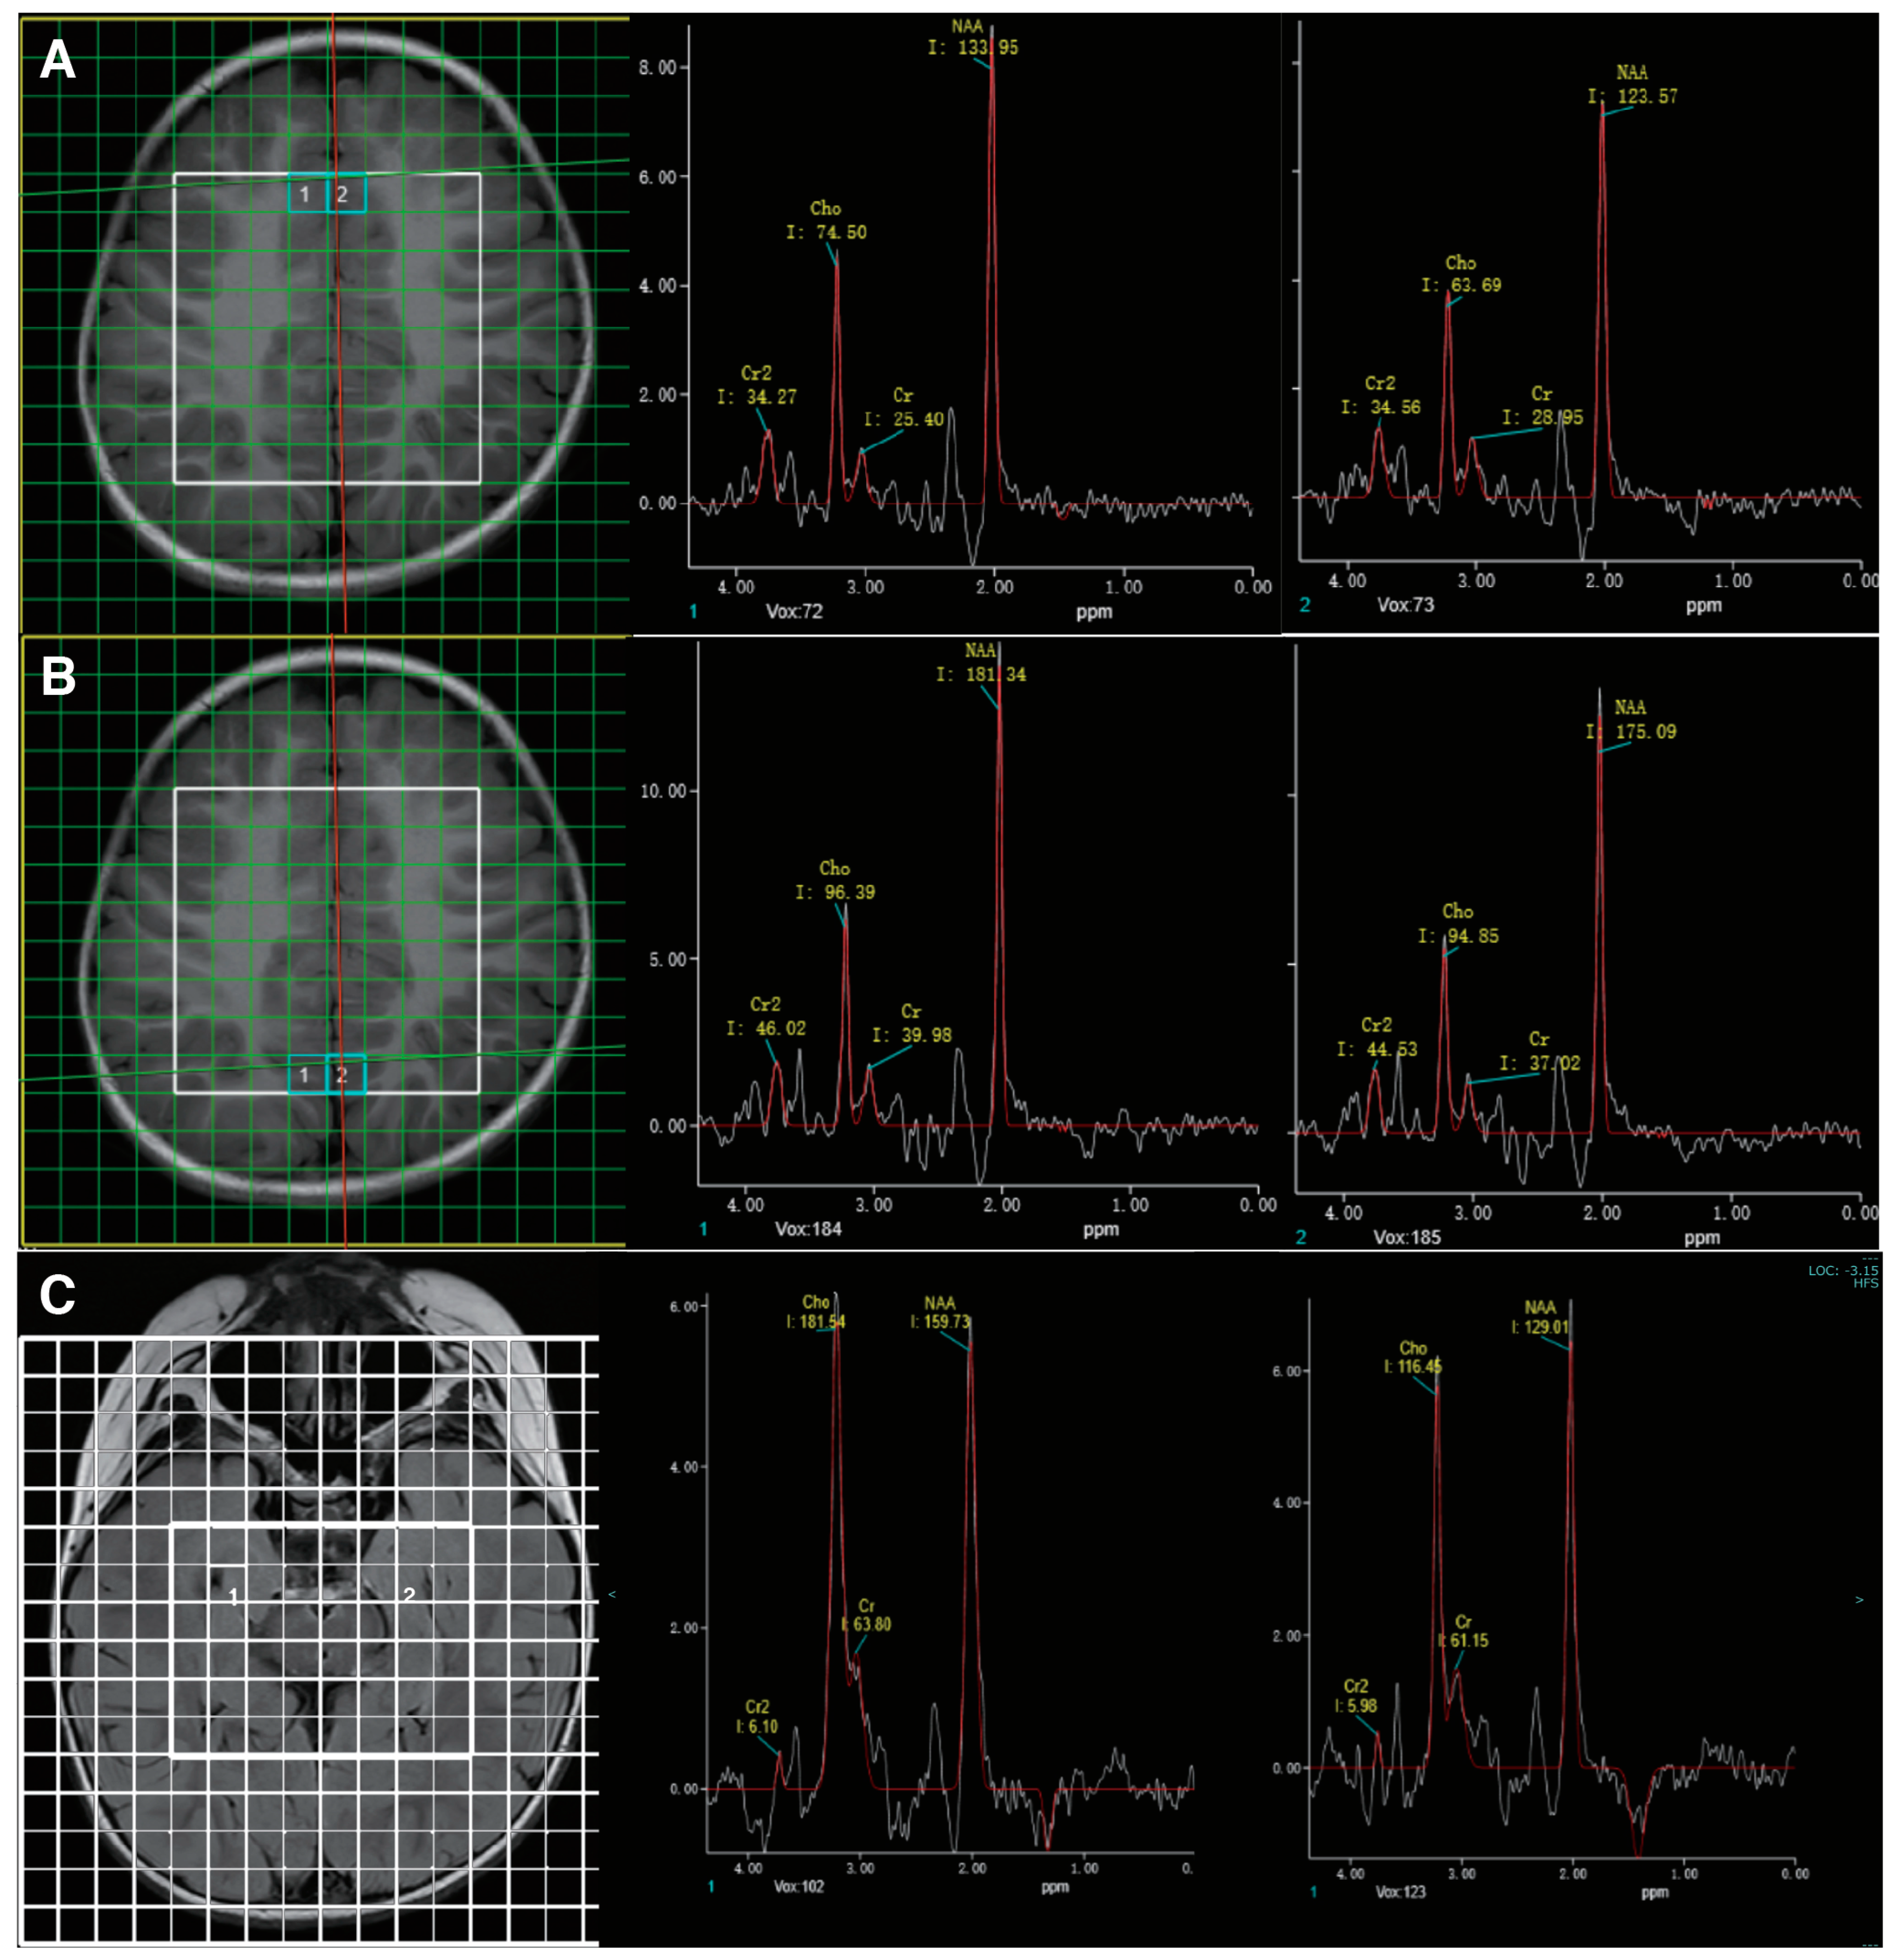

3.1. Case Presentation

3.3. Treatment and Follow-Up